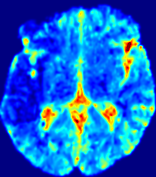

Figure 4: PIANO feature maps for another patient in the ISLES 2017 training set, where the lesion is located in the right hemisphere. Top row: segmented stroke lesion region (white) on different slices. The corresponding slices for the PIANO feature maps are shown in the following rows.

For a better insight into an estimated velocity field 𝐕𝐕{\bf{V}} and diffusion field 𝐃𝐃{\bf{D}}, we compute the following maps: (1) 𝐕rgbsubscript𝐕𝑟𝑔𝑏{\bf{V}}_{rgb}: Color-coded orientation map of 𝐕=(Vx,Vy,Vz)T𝐕superscriptsuperscript𝑉𝑥superscript𝑉𝑦superscript𝑉𝑧𝑇{\bf{V}}=(V^{x},V^{y},V^{z})^{T}, obtained by normalizing 𝐕𝐕{\bf{V}} to unit length and mapping its 3 components to red, green, blue respectively; (2) 𝐕2subscriptnorm𝐕2\|{\bf{V}}\|_{2}: 222 norm of 𝐕𝐕{\bf{V}}; (3) D𝐷D: scalar field in Eq. 5.

Fig. 3 and Fig. 4 show the PIANO feature maps estimated from two ISLES 2017 patients: all are highly consistent with the lesion in both cases. Details of the blood flow trajectories are revealed in 𝐕rgbsubscript𝐕𝑟𝑔𝑏{\bf{V}}_{rgb} by the ridged patterns and the sharp changes of colors in the unaffected (right) hemisphere, while the flat patterns appearing within the lesion provide little directional information about the velocity and indicate low velocity magnitudes. Velocity magnitudes are more directly visualized via 𝐕2subscriptnorm𝐕2\|{\bf{V}}\|_{2}, from which one can easily locate the lesion where 𝐕2subscriptnorm𝐕2\|{\bf{V}}\|_{2} is low. D𝐷D also indicates lower diffusion values in the lesion, though with less contrast potentially due to the fact that it captures the accumulated effect of CA diffusion at the voxel-level.